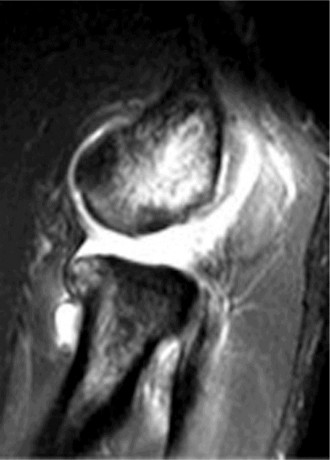

Treat a patient with axillary neuropathy? CASE 24 A 21-year-old, right-hand-dominant, male, college swimmer presents to clinic complaining of gradually worsening right shoulder pain for the past 6 months. He notes that his times at swim meets have been slowing with the onset of the pain but that he is still able to swim through the pain. Physical examination reveals: decreased muscle bulk over the infraspinatus fossa of the right shoulder compared with the contralateral side (shown in Fig. 2–64), full active range of motion, strength 4/5 for external rotation but otherwise normal strength, mild pain with cross-body adduction of the right shoulder, and mild tenderness to palpation over the AC joint. Imaging is shown in Figure 2–65.

Figure 2–64

Figure 2–65

The correct answer is (D). This patient’s atrophy of the infraspinatus muscle leading to weakness with external rotation and with preserved strength in the other rotator cuff muscles is likely due to neuropathic process of the suprascapular nerve at a

point along its course off the upper trunk of the brachial plexus on its way to innervate the supraspinatus and infraspinatus muscles. Choice A is incorrect as rotator cuff tendinitis would not present with muscle atrophy. AC joint arthritis (Choice C), while often presenting with tenderness to palpation over the AC joint and pain with cross body adduction, is also not usually associated with infraspinatus atrophy and would likely present with narrowed joint space or AC joint osteophytes on plain films, unlike this patient. Choice B is incorrect as the patient has full active range of motion, while adhesive capsulitis would more likely present as decreased active and passive range of motion.

You send the patient for an MRI, which is shown in Figure 2–66.

Figure 2–66

The correct answer is (C). The patient’s clinical examination findings of isolated

weakness in external rotation and atrophy of the infraspinatus muscle point to suprascapular nerve entrapment at a location past the exit point for the branch to the supraspinatus muscle. Also, MRI reveals a posterior labral tear with a paralabral cyst that is compressing the suprascapular nerve at the spinoglenoid notch. Choice A, while fitting with the patient’s clinical examination, does not fit with the MRI showing paralabral cyst. Choices B and D are incorrect because entrapment of the suprascapular nerve at the suprascapular notch by scapular body fracture or by the transverse scapular ligament (more common) would lead to weakness/atrophy in both supraspinatus and infraspinatus muscles as the suprascapular notch is proximal to the nerve branch point to the supraspinatus muscle.